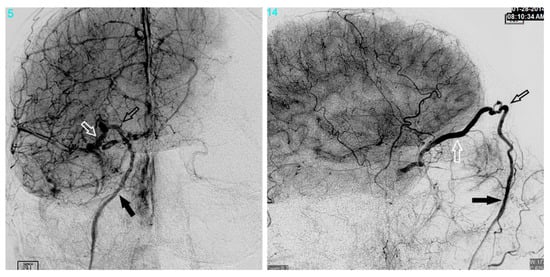

Figure 10. Demonstrates a right sided direct carotid cavernous fistulas (CCF). An occlusion balloon is placed within the right cavernous internal carotid artery (ICA) (white arrow) across the fistula site. Coils are placed within the intercavernous sinus (black solid arrow) through a transvenous inferior petrosal sinus (IPS) approach (white solid arrow). Note the superior petrosal sinus (black arrows), in the lateral projection, with its acute angle off the transverse sinus.

12. Transarterial Via the Cavernous Segment of the ICA (Direct CCF) or Via ICA/ECA Meningeal Branches (Dural CCF)

In the setting of direct CCFs, the tear in the cavernous segment of the ICA provides an endovascular route to the CS. A primary transarterial approach can often be used to embolize these fistulas. Prior to attempting a primary embolization of the fistula, a complete angiogram should be completed, and if adequate cross-filling is identified, a balloon test occlusion (BTO) is recommended. If the patient remains neurologically unchanged, the most effective treatment is often complete ICA occlusion. It is important to remember that the carotid occlusion should extend across the fistula site both proximally and distally to prevent retrograde filling of the fistula from collateral circulation. In the case of failed BTO, the fistula must be treated while maintaining patency of the ICA. In this case, the authors often use a two-catheter system with a microcatheter in the cavernous sinus for embolization and a Scepter balloon catheter (MicroVention, Tustin, CA, USA) to protect the ICA. Using roadmapping technique, a microsystem is then navigated through the tear in the cavernous ICA into the affected CS. An occlusion balloon, or a stent, is placed within the cavernous ICA across the fistula site to protect the ICA during embolization. Coils, Onyx (Covidien, Irvine, CA, USA), or a combination of both are then used to obliterate the fistula. Alternatively, in some cases of direct CCF, a combined transarterial and transvenous approach is the safest and most effective way to embolize the fistula. Figure 10 demonstrates a right sided direct CCF with venous drainage through the intercavernous sinus into a dilated left CS. In this case, the authors first navigated a Hyperform balloon (Covidien, Irvine, CA, USA) across the tear in the right ICA. Next, a microsystem was navigated through the left IPS, into the left CS, and subsequently into the intercavernous sinus. With the balloon inflated to prevent coil migration into the right ICA, the intercavernous sinus was embolized with coils, effectively obliterating the fistula. Final angiograms showed no evidence of residual fistula, and the patient had complete resolution of her preoperative symptoms.